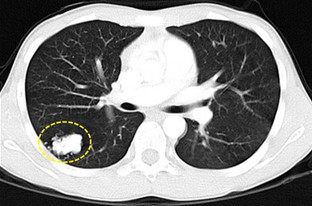

3)肺部肿瘤:分良性肿瘤(炎性假瘤、错构瘤)、恶性肿瘤(肺癌或肺继发转移癌)。大家担心的是肺癌,肺癌患者常常发生于长期吸烟、年龄40~50岁以上、有刺激性干咳或咳嗽咳痰、痰中带血、胸闷、胸痛、体重明显下降、乏力等不适症状,实验室检查血肿瘤标志物可以升高、痰或肿块穿刺活检、纤维支气管镜活检可找到癌细胞,影像学有特殊表现(如胸部CT提示肺部结节呈“分叶状”或有“毛刺征”,转移性肺癌其肿块边缘一般比较光滑,肺内易出现多个类似结节)。若明确诊断肺癌,则应及时到肿瘤专科行规范治疗,选择手术或放化疗或靶向治疗等治疗手段,而不应该道听途说病急乱投医,贻误病情。